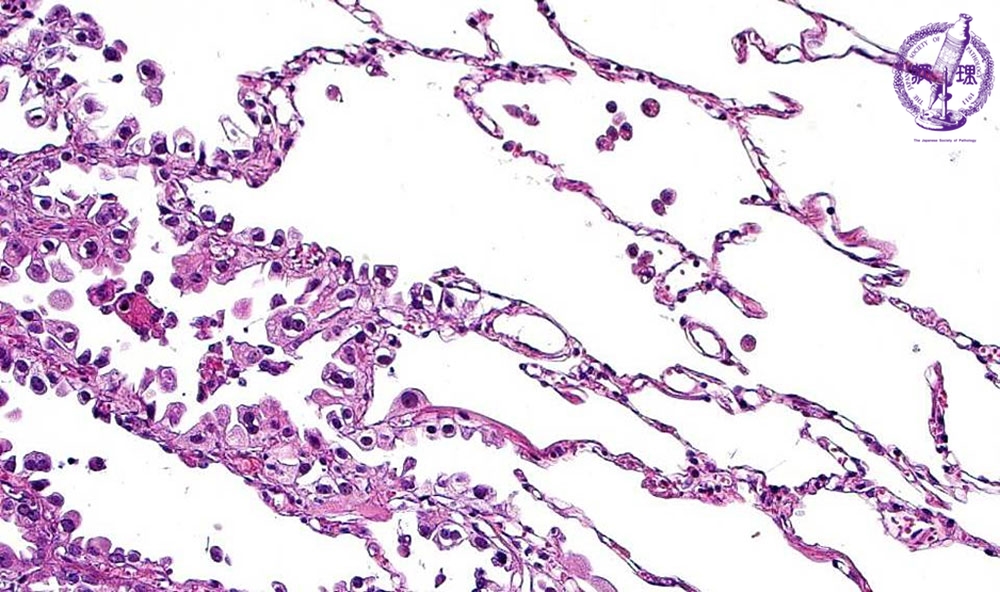

非小細胞肺癌(腺癌)ミクロ像(HE強拡大)

ミクロ像(HE強拡大):腺癌の辺縁では、既存の肺胞上皮細胞を置換性しながら増殖することが多く、肺胞構造を破壊していない。 正常上皮との境界(点線)は明瞭である。